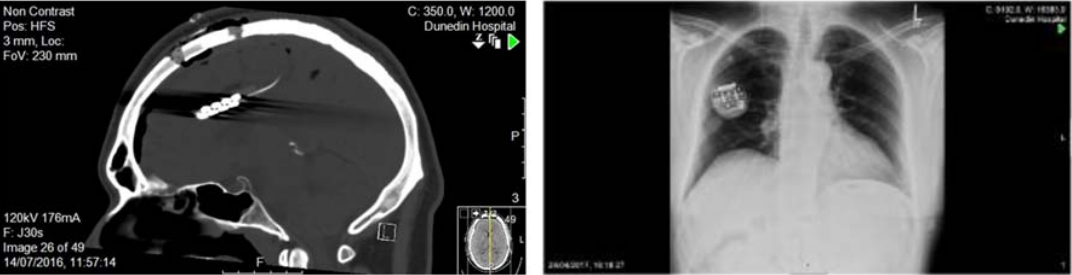

这篇文章研究了使用皮层植入电极刺激背侧前扣带回(rACC),治疗酒精成瘾的有效性和可行性。八名患者(四名男性和四名女性)先接受了经颅磁刺激(rTMS)的治疗评估脑部刺激效果,随后通过手术将两个电极植入患者脑内以获得更持久的效果。此外还在患者锁骨下方皮下植入了脉冲发生器(IPG)作为电极的"开关"。

一半的患者出现了不良反应(如下表)。4号5号患者由于感染需要将IPG移除。4号患者在手术后3天出现精神症状。8号出现了右额静脉梗塞,并伴有斑点状的出血性改变,术后1天造成短暂的左侧肢体无力,偏瘫在3周后完全缓解,该患者在手术后26周有两次癫痫发作,需要停用IPG。6号患者在术后回家后的3周内表现出鲁莽的冲动行为,在术后回家后的3个星期里,IPG的激活被推迟了一个月。作者对此的解释是,4号6号的不良反应发生在IPG激活以前,可能是围手术期压力(perioperative stress)导致,并且4号入院时隐瞒了精神分裂症病史。8号产生的不良反应属开颅手术已知风险,4号5号的感染若使用万古霉素而不是常规的预防性抗生素,应该避免。